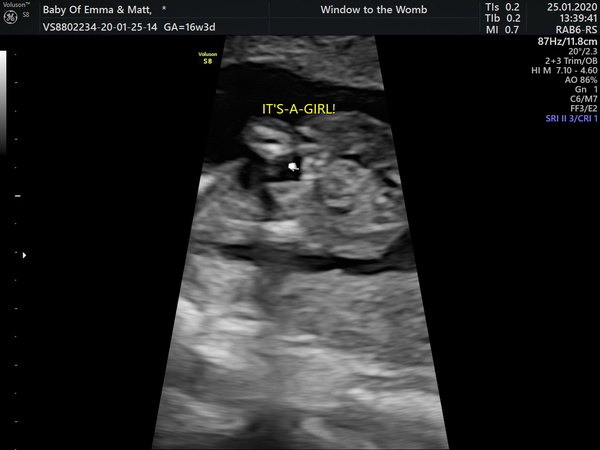

I'm 16+3 and went today privately to have my gender scan. I've had put in my head since day one that we'll be having a boy, today at the scan we got told we'd be having a little girl. We're very much in shock because all we've been convinced by people is it's a girl 🤣. We're happy and we didn't mind the gender as long as they were heathy. The only thing that's on my mind was that it took a while for the sonographer to figure out the gender and I had to cough a few times to get her to budge! Me and oh could have sworn we saw a little penis in the photos but the sonographer saw the three lines for a burger for a girl. I've attached the scans and the photos we thought were a boy. Is it the placenta that we saw? I feel awlful questioning it and we are happy but would be happy to hear your thoughts!

Hey! We had a gender scan at 17+1 and his seems to be a lot more prominent and obvious, so I think in comparison you have a girl:) but maybe wait til you've had another scan to do any announcements x